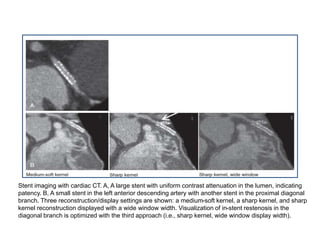

Stent imaging with cardiac CT. A, A large stent with uniform contrast attenuation in the lumen, indicating

patency. B, A small stent in the left anterior descending artery with another stent in the proximal diagonal

branch. Three reconstruction/display settings are shown: a medium-soft kernel, a sharp kernel, and sharp

kernel reconstruction displayed with a wide window width. Visualization of in-stent restenosis in the

diagonal branch is optimized with the third approach (i.e., sharp kernel, wide window display width).